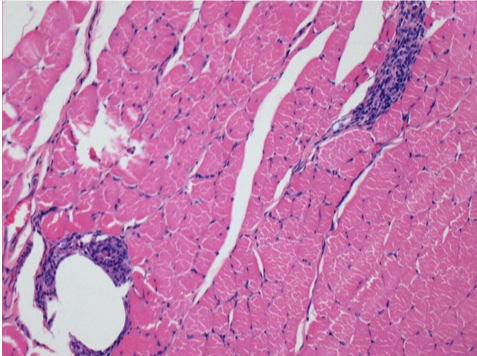

Control

Comentario: Nada que declarar después de la inyección de solución salina.

L: Pretibial-Sin tratamiento

R: Pretibial-Después de 0,1 ml de NaCl 0,9% IM